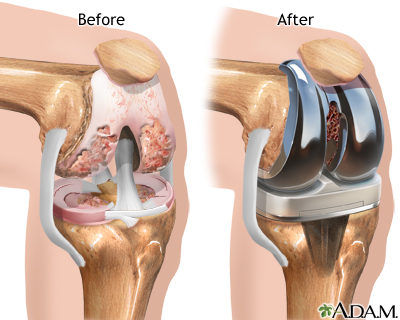

The most common cause of knee damage that leads to knee replacement is osteoarthritis. Osteoarthritis is a degenerative disease of the bones of the knee. It causes the surfaces of the knee joint to become irregular and rough, preventing smooth painless motion of the knee joint.

The operation is performed under general anesthesia. The orthopedic surgeon makes an incision over the affected knee. The patella (knee cap) is moved out of the way, and the surgeon shaves the heads of the femur and tibia to remove any rough parts. This allows helps the prosthesis to adhere better. The two parts of the prosthesis are implanted into the thigh bone and the tibia bone using a special bone cement.